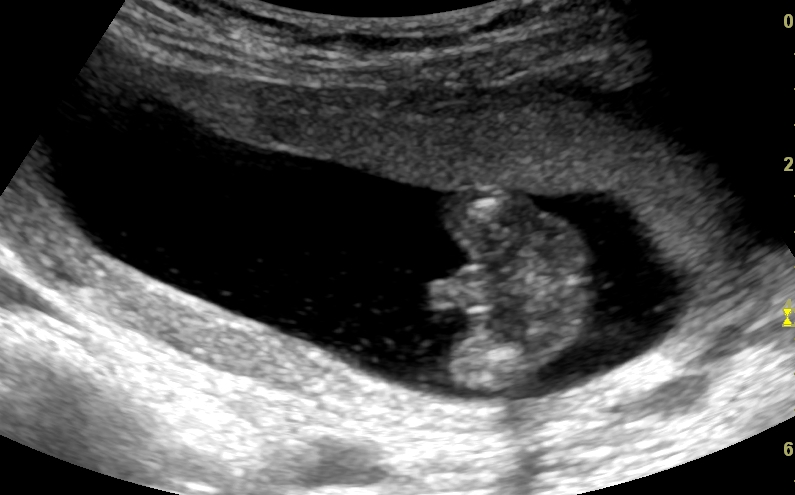

Hi, I got my u/s, and to our surprise the technician said we are expecting a boy! The nub theory said girl, everyone here was guessing girl LOL

Anyway, we are really happy!! I am already packing all of the nb girl clothes, and giving them away to my friend....but just wanted to make sure one more time! This is boy indeed right? The picture says it all! But I am not an expert! Thanks!

Attachment 14346